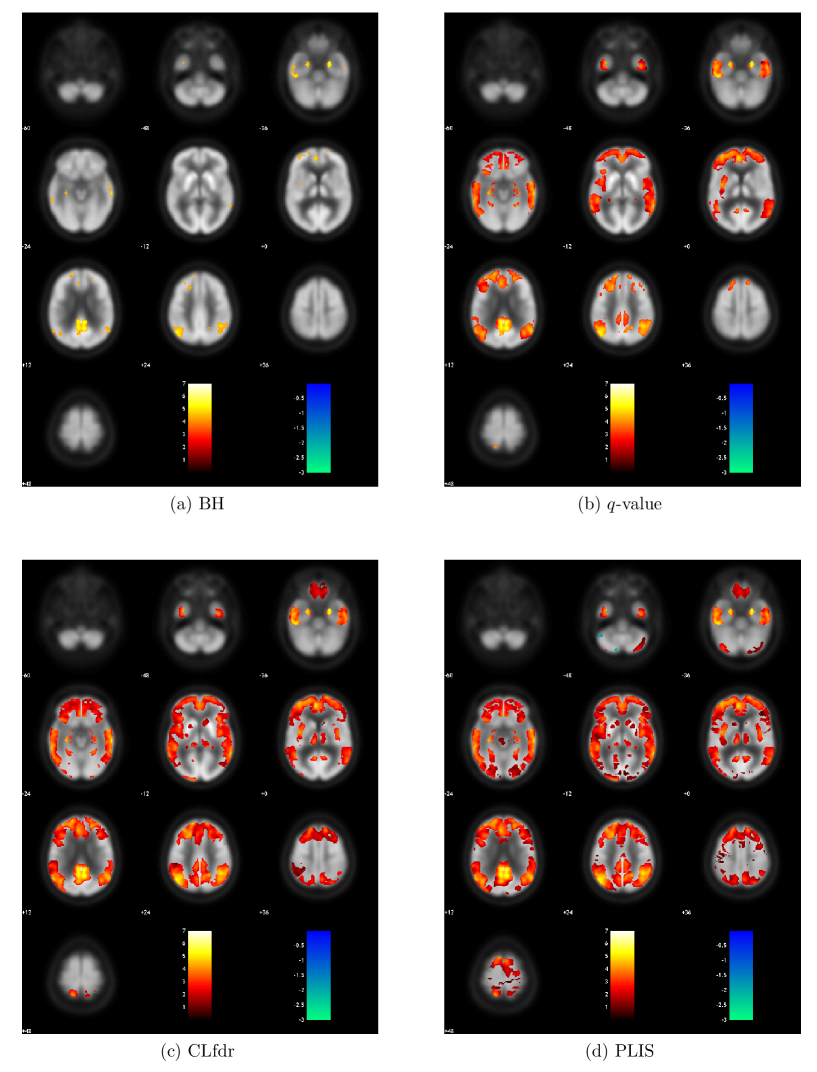

Figure 4 shows the z𝑧z-values (obtained by comparing CMRgl values between NC and MCI) of all the signals claimed by each procedure. Figure 5 summarizes the number of voxels that are claimed as signals by each procedure. We can see that PLIS finds the largest number of signals and covers 91.5%, 97.2% and 99.9% of signals detected by CLfdr, q𝑞q-value and BH, respectively. It is interesting to see that the PLIS procedure finds more than 17 times signals as BH, twice as many signals as q𝑞q-value, and about 20% more signals than the CLfdr procedure.

Refer to caption

Figure 4: Z𝑍Z-values of the signals found by each procedure for the comparison between NC and MCI.